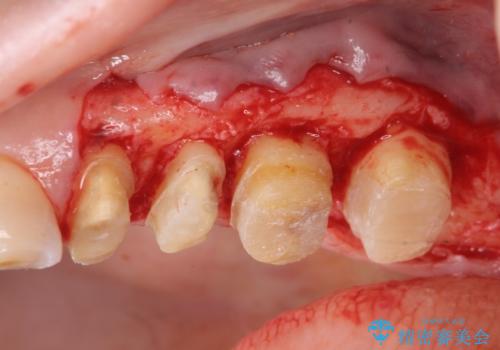

虫歯の深化により根管治療、歯周外科手術を行い歯肉の状態を改善し精密なセラミッククラウンを製作する治療を計画します。

セラミック治療の長期的な予後を見込むために、根管治療、歯周外科を行いクラウン装着前の環境を整えておくことが肝要です。